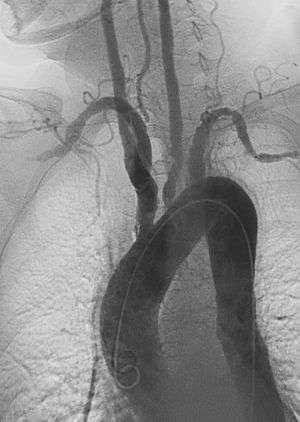

| Left anterior oblique angiographic image of Takayasu's arteritis showing areas of stenosis in multiple great vessels | |

Although the cause of Takayasu arteritis is unknown, the condition is characterized by segmental and patchy granulomatous inflammation of the aorta and its major derivative branches. This inflammation leads to arterial stenosis, thrombosis, and aneurysms.[3] There is irregular fibrosis of the blood vessels due to chronic vasculitis, leading to sometimes massive intimal fibrosis (fibrosis of the inner section of the blood vessels).[5] Prominent narrowing due to inflammation, granuloma, and fibrosis is often seen in arterial studies such as magnetic resonance angiography (MRA), computed tomography angiography (CTA), or arterial angiography (DSA).

Diagnosis is based on the demonstration of vascular lesions in large and middle-sized vessels on angiography, CT, or magnetic resonance angiography.[9]

Contrast angiography has been the gold standard. The earliest detectable lesion is a local narrowing or irregularity of the lumen. This may develop into stenosis and occlusion. The characteristic finding is the presence of "skip lesions," where stenosis or aneurysms alternate with normal vessels. Angiography provides information on vessel anatomy and patency but does not provide information on the degree of inflammation in the wall.[9]